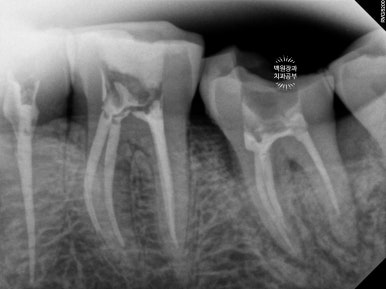

처음 오셨을 때의 상태입니다.

엑스레이를 같이 참고해 보셔야 하는데요,

양쪽 위 큰 어금니가 모두 발치된 상태로 오래 지내신 분이었어요.

보시면 상대적으로 아래 앞니가 머리가 매우 조금만 남아있는 것을 보실 수 있으실텐데요,

아래 앞니가 저렇게까지 극적으로 사라지게 된 경위를 살펴보자니

위 어금니가 없는채로 오래 지내시다보니

주로 앞니로 식사를 하게 됩니다.

위 앞니는 금속-도재 고정성보철물(PFM bridge)로 제작이 되어있는데요, 도재가 씌워진 보철물에 의해 아래 앞니의 마모가 가속화되고

결국 아래 앞니의 머리가 없어질때까지 깨지고 닳고.. 그런 과정을 거치게 된 것이죠.

대구치의 상실은 교합의 붕괴에 가장 큰 영향을 주는 것 같습니다.

아래 앞니의 마모도가 상당히 심합니다.

치과에서 교모(attrition)라고도 하는데요, 머리가 닳아 없어지다보니 치아 내부의 신경관이 드러나게 되고

그렇게 발생한 치통을 해결하기 위해 신경치료를 모두 받으셨던 흔적도 보여요.